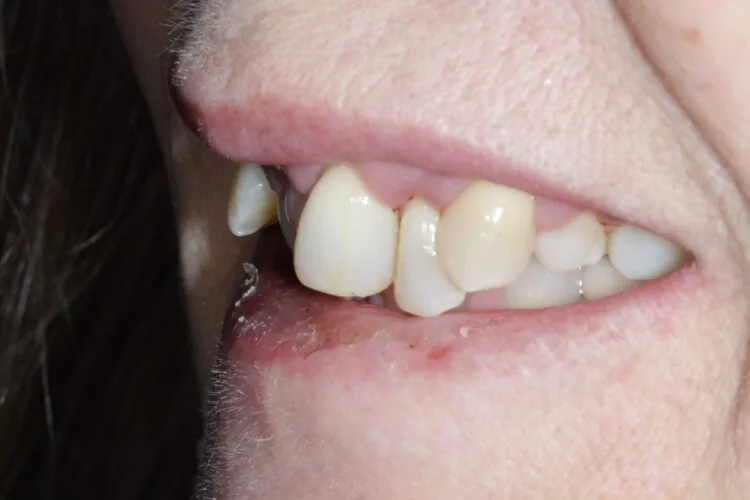

A woman in her mid-50s presented with the desire to improve her smile. She had not attended dental appointments for several years and felt ashamed of her teeth due to longstanding neglect. At the time of presentation, she had significant periodontal deterioration, particularly involving the upper four anterior teeth, which exhibited bone loss and mobility. Although she initially requested orthodontic treatment, this was not viable due to the advanced periodontal condition

Presenting condition

A comprehensive periodontal examination revealed widespread pocketing and clinical signs of mobility in the anterior region. The upper central and lateral incisors were the most severely affected, and they showed persistent instability despite improvements elsewhere. Generalised recession and attachment loss were confirmed, with periodontal charting from September 2023 and follow-up data in November 2023 demonstrating the extent of disease and its subsequent management.

Pre-treatment images